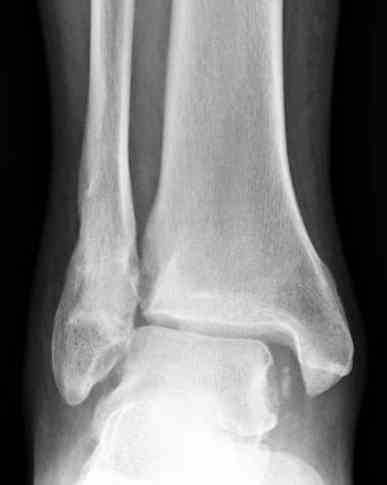

Здесь представлено решение похожей проблемы. Больной в течение года лечился консервативными мерами, и боли в голеностопе были основным показанием к операции.

Проведена обычная стандартная процедура по исправлению неудовлетворительного состояния голеностопного сустава, где кроме удлинения малоберцовой с применением compression tension device за проксимальный конец пластины, проведено замещение трикортикальным графтом из крыла, освобождение синдесмоза и медиальной щели от

фибротических масс с фиксацией.